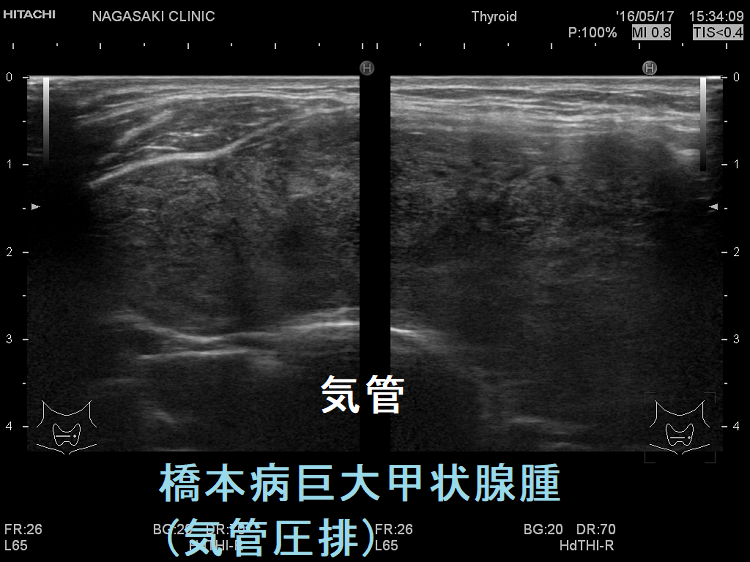

橋本病などの巨大甲状腺腫

海外では、閉塞性睡眠時無呼吸症候群(OSAS)治療のために、肥満者あるいは非肥満者の巨大甲状腺腫を摘出して改善を認めた論文があります(Monaldi Arch Chest Dis. 2006 Mar;65(1):52-5.)(World J Surg. 2014 Aug;38(8):1990-4.)。

しかし、日本では、腫瘍もない甲状腺を閉塞性睡眠時無呼吸症候群(OSAS)治療のために全摘出するのは難しいと思います。(甲状腺外科が納得しないでしょう)